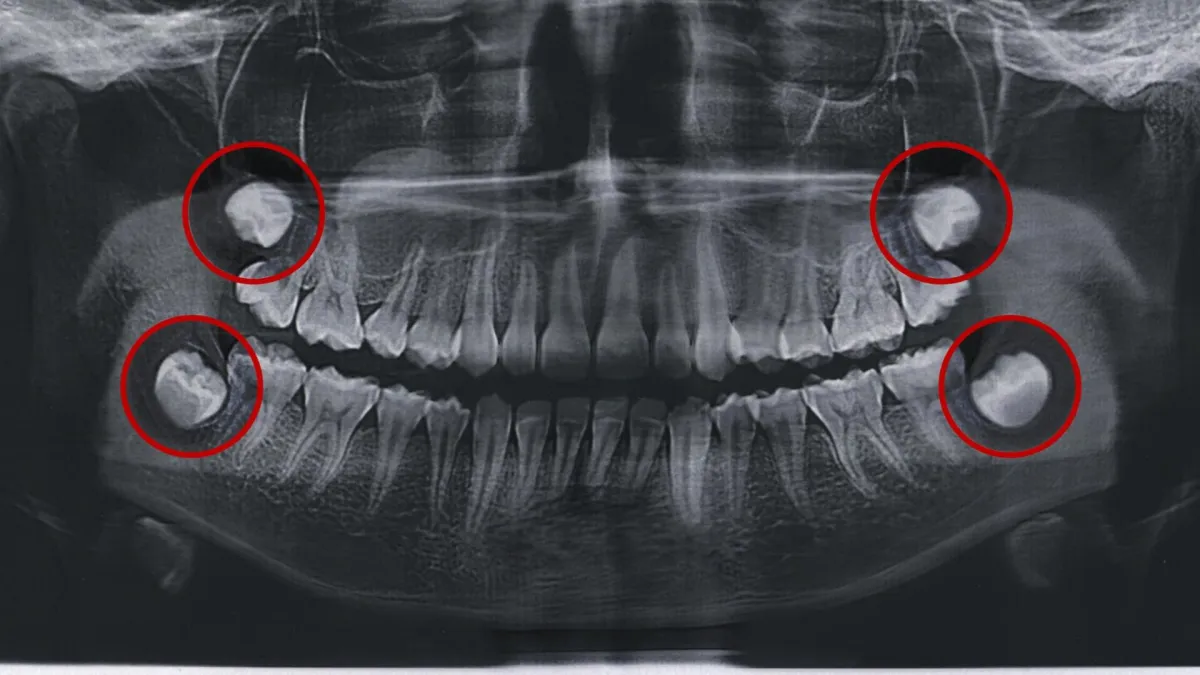

#10 - Wisdom Teeth Become Inflamed

Wisdom teeth are notoriously painful. They seem to come whenever they please, and when they do, they can easily wreak havoc. Pericoronitis is an infection that can occur when your wisdom teeth don’t come in properly. The risk of this spreading is too high to neglect.

If you get it, you’ll know because of your irritated gums in that area, as well as possible bad breath. You'll likely feel a painful pressure in your wisdom teeth area also. See a dentist as soon as possible to get this resolved.